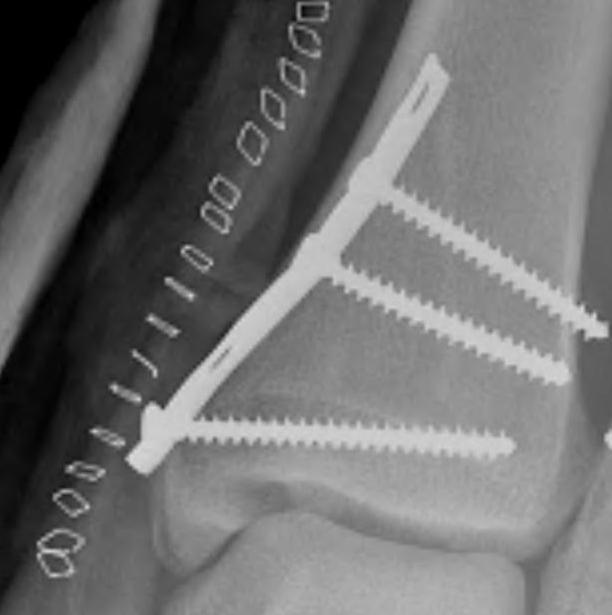

![]() |

Type D: Vertical fractures |

Tension band wire

AO surgery reference medial malleolus cerclage wire